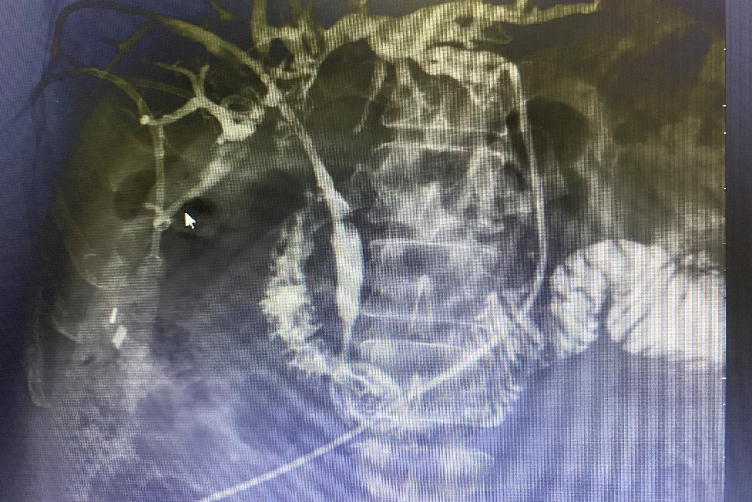

术前:经PTCD管胆道造影

术中:植入两枚8mmX80mm支架